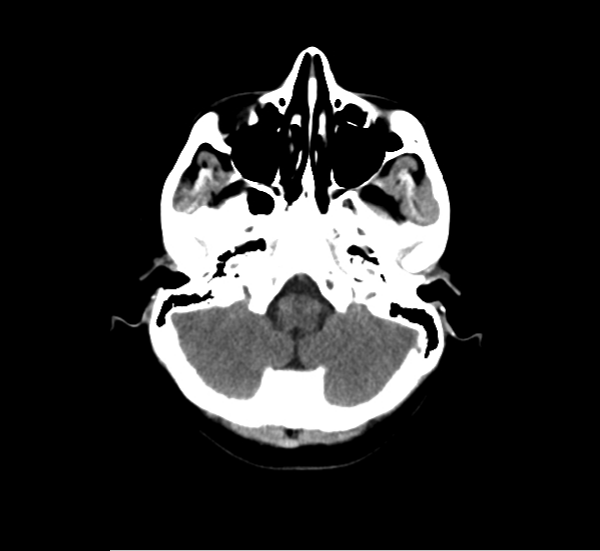

CT Brain Anatomy